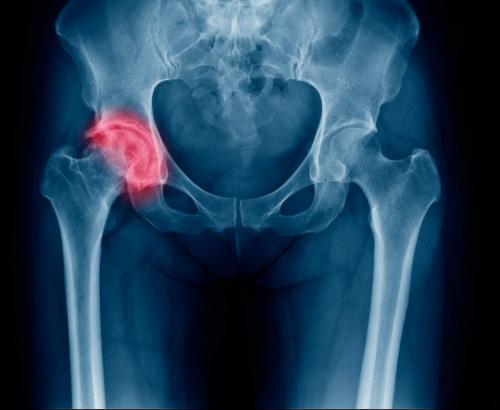

Асептический некроз головки бедренной кости.

Тазобедренное сочленение – это самое крупное и наиболее нагруженное сочленение, нарушение работы которого существенно ограничивает подвижность человека, снижает качество его жизни.Если человек испытывает, то это может свидетельствовать о наличии патологического процесса, приводящего к разрушению костной или хрящевой ткани.